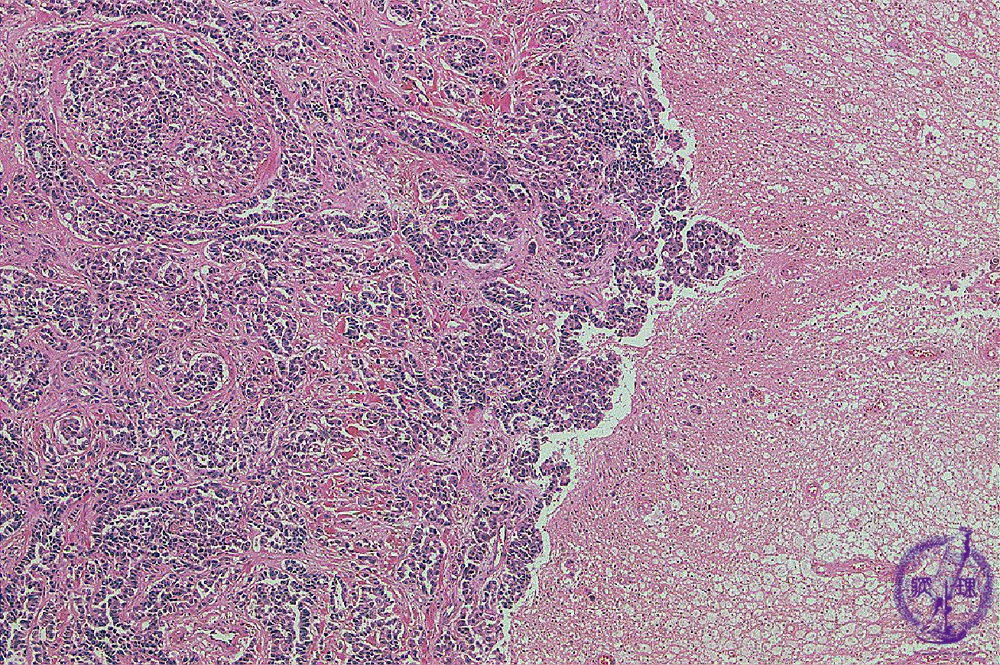

Microscopic findings (H.E. low magnification): Atypical epithelial cells showing glandular structures invaded into the cerebral parenchyma, but the invasive front was clear.